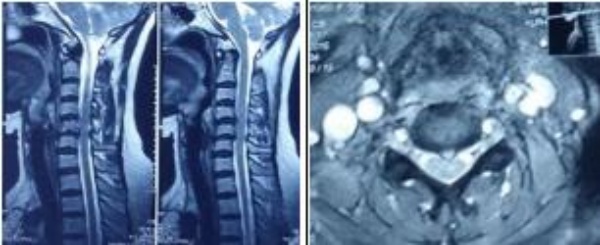

Tất cả bệnh nhân được chụp Xquang qui ước và chụp cắt lớp để phân tích thương tổn xương, đánh giá sự mất vững, đo tầm vận động cột sống cổ, chụp cộng hưởng từ để xác định tổn thương đĩa đệm, mức độ thoát vị, thương tổn tủy cổ.

Đặc điểm chẩn đoán hình ảnh: Trên Xquang tầm vận động cột sống cổ (ROM) trung bình tư thế cúi hết cỡ 18.040 ± 7.840 (5 – 350), ngửa hết cỡ 30.000 ± 11.520 (11 – 350). Trên phim MRI có 57.15% thoát vị tại vị trí C5C6, 18.18% thoát vị tại mỗi vị trí C4C5 và C6C7, còn lại 6.49% tại C3C4. Tương ứng với tổn thương trên hình ảnh cộng hưởng từ, chúng tôi tiến hành phẫu thuật thay đĩa đệm nhân tạo cho 59 trường hợp với tổng số 77 đĩa đệm ESP Prosthetic. Thời gian phẫu thuật trung bình 95.28 ± 21.04 phút/1 đĩa, 138.33 ± 34.33 phút/2đĩa và 230.00 ± 42.43 phút/3 đĩa.